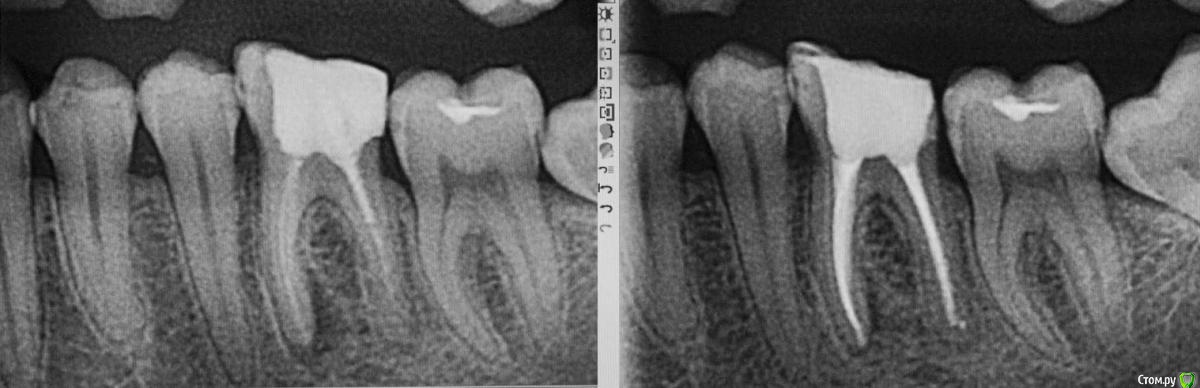

M@estro Опубликовано 9 июля, 2015 Автор Поделиться Опубликовано 9 июля, 2015 Тоже подниму тему. Травму отрицает, жалобы на потемнение. Витальность "-", перкуссия "-" , на рентгене подсказка - есть латераль. Вперёд, мыть ! 60 апекс, гибрид паковка. 1 час с пломбой 7 Ссылка на комментарий